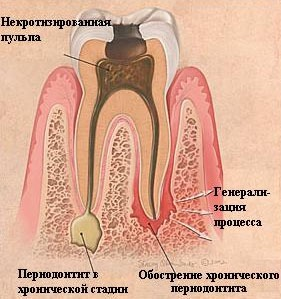

Периодонтит

– это воспаление периодонта, окружающих зуб тканей.

Существует множество факторов возникновения воспалительного очага в периодонте, главным из которых является осложнение кариеса (исход не леченного пульпита). Незалеченный кариозный канал – это прекрасный путь инфекции к здоровым тканям. Случается, что причиной воспаления периодонта становится травма зуба или ожог его тканей пастой с мышьяком, но гораздо частой причиной является пустой или плохо пролеченный корневой канал.

Периодонтит симптомы, патогенез периодонтита.

Любой из вышеперечисленных факторов приводит к тому, что инфекция по корневым каналам спускается к верхушкам корней и достигает периодонта. Вследствие инфицирования возникает гранулёма или киста, которые в свою очередь приводят к разрушению не только связки, фиксирующей зуб в челюсти, но и костной ткани. Поэтому симптомами периодонтита являются:

- подвижность зуба,

- острая, пульсирующая, хорошо локализованная боль, усиливающаяся при жевании или постукивании по десне.

Специалисты условно разделяют течение острого периодонтита на две фазы:

- фаза интоксикации – самое начало болезни, характеризующееся ноющими болями и синдромом «большого зуба» (зуб как будто вырос, стал выше), и фаза выраженного экссудативного процесса.

- вторая фаза характеризуется появлением высокой температуры, интенсивными пульсирующими болями, болями при накусывании (к зубу бывает не притронуться), десна может отекать, образуется припухлость (флюс), когда гной прорывается через десну боль утихает, образуется свищ.

Общий анализ крови больного определяет повышение СОЭ. В тканях зуба происходит расплавление связочного аппарата зуба и околозубных тканей. Гнойные массы постепенно формируют гранулёму или кисту. Хроническое течение периодонтита нередко трудно диагностируется, так как имеет сходную симптоматику с другими заболеваниями зубов. Зачастую, люди даже и не догадываются о своём заболевании, не принимая всерьёз небольшие боли или чувство неудобства, с такими симптомами они редко обращаются к врачу, нередко заболевание выявляется случайно при рентгенографии соседних зубов. И как следствие – страдают почки и сердце человека, так как организм отравляется продуктами распада собственных тканей, особенно если таких зубов много и они часто воспаляются. Для выявления скрытых (спящих) очагов очень помогает панорамная рентгенограмма, рекомендуется делать хотя бы раз в два года. |

Разновидности периодонтита:

- хронический фиброзный периодонтит

- хронический гранулирующий периодонтит

- хронический гранулематозный периодонтит

Конечно, самым простым методом лечения данного заболевания является удаление поражённого зуба и назначение курса антибиотиков, но наши стоматологи постараются сохранить Ваш зуб и применят терапевтические методы лечения. Они направлены на купирование воспаления, дезинфекции и восстановлении повреждённых тканей, герметизации каналов для предотвращения повторного инфицирования, а в итоге – на полное восстановление функций зуба.

Конечно, самым простым методом лечения данного заболевания является удаление поражённого зуба и назначение курса антибиотиков, но наши стоматологи постараются сохранить Ваш зуб и применят терапевтические методы лечения. Они направлены на купирование воспаления, дезинфекции и восстановлении повреждённых тканей, герметизации каналов для предотвращения повторного инфицирования, а в итоге – на полное восстановление функций зуба.

При лечении периодонтита используется методика, сходная с технологией лечения пульпита:

При лечении периодонтита используется методика, сходная с технологией лечения пульпита:

- Прежде всего, коронку зуба раскрывают, чтобы открыть доступ к корневым каналам.

- Затем под прикрытием антисептических препаратов из каналов начинают извлекать поражённые ткани. Эту манипуляцию производят аккуратно, дробно, постепенно продвигаясь к верхушке корня. Извлекая очередную порцию ткани, оборудование промывают в антисептике.

- В конце работы тщательно промывают весь канал и закладывают в него лекарственную пасту.

- Поверх пасты наносят временную пломбу.

- Через несколько дней в канал закладывают новую порцию пасты и вновь пломбируют зуб. Эту операцию производят до тех пор, пока воспалительный очаг окончательно не затихнет.

Если медикаментозное лечение результатов не даёт, и киста не рассасывается, прибегают к хирургическому вмешательству – производят резекцию верхушки корня зуба, цистотомию и цистэктомию (различные способы удаления кисты).

Все эти меры направлены на сохранение зуба пациента. В результате лечения симптоматика полностью исчезает, а разрушенная костная ткань восстанавливается в течение года. В случае если консервативное лечение не принесло результатов, зуб удаляют. Протезирование или имплантацию проводят только после окончательного восстановления костной ткани, что потверждается рентгенологическим обследованием ( по снимку).